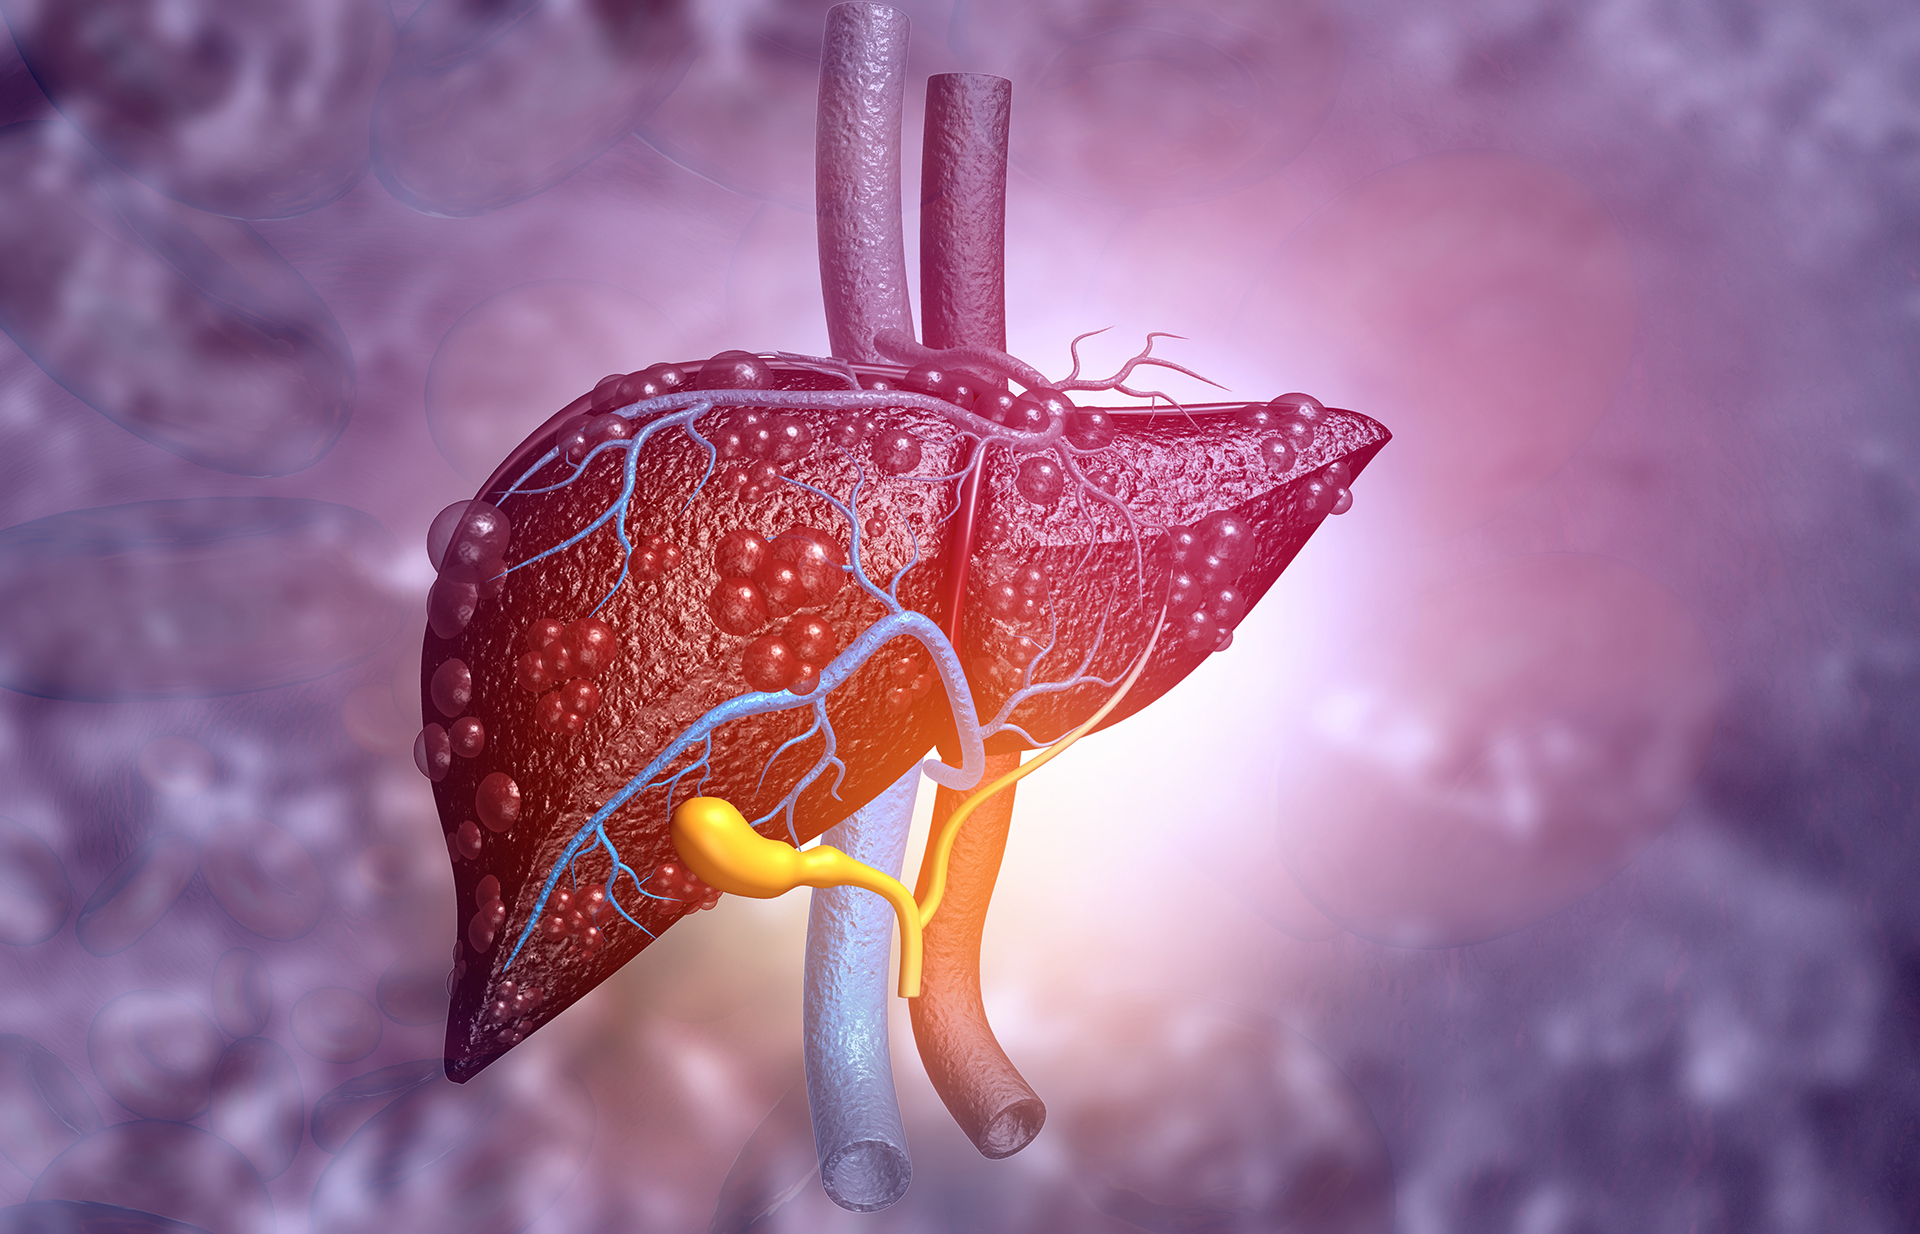

Healthy Liver: लीवर हमारी बॉडी के सबसे महत्वपूर्ण अंगों में से एक है, जो ब्लड फ्लो को डेटोक्सिफिकेशन करने के साथ पाचन के लिए पित्त का उत्पादन करने, एनर्जी स्टोरेज करने का कार्य करता है। लेकिन आजकल की अनहेल्थी लाइफस्टाइल , प्रोसेस्ड फूड्स खटराब दिनचर्या के चलते हमारे लीवर पर बुरा असर पड़ता है। जिससे हेल्थ संबंधी समस्याएं हो सकती हैं। ऐसे में आज हम आपको लीवर को हेल्थी बनाए रखने के लिए कई तरह की टिप्स बताएँगे।